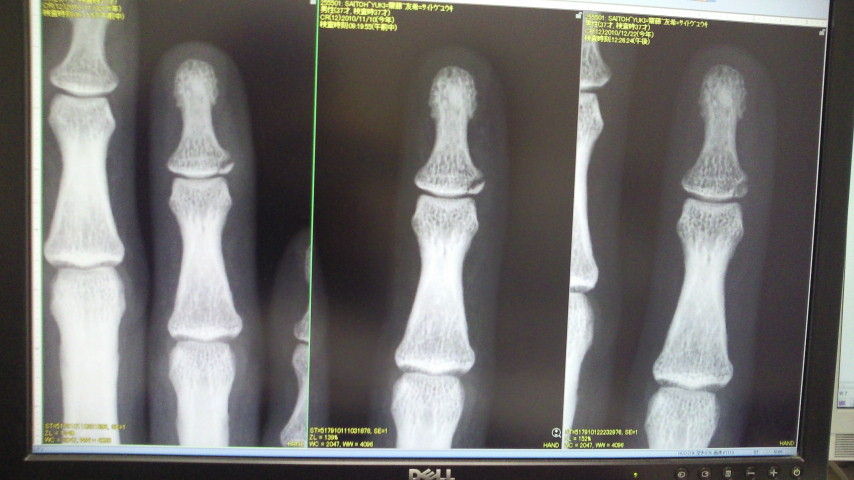

レントゲンを撮って診てみたら骨もくっついていて全く問題なしとのこと。